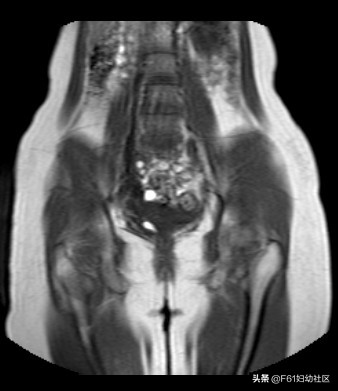

此病人为22岁青年女性,因月经期延长3月就诊,经前一周少量血性分泌物三次至月经来潮。超声提示此患者盆腔可见两个子宫体部及两个子宫颈,附件未见异常。下图为此患者MRI图。

上图为子宫T2WI横断位,能看到两个宫体,子宫内膜增厚。